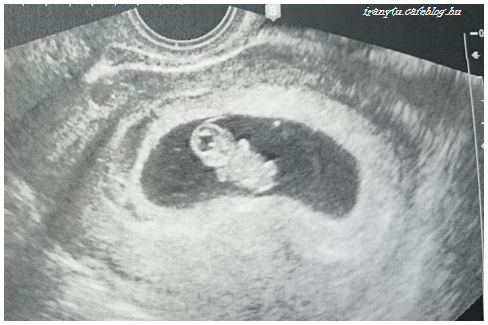

A dolgok haladnak a maguk útján. Azt a bizonyos UH kontrollt követően – ahol is ugye kiderült, hogy mégiscsak ott az a baba – ha már ott voltam, megcsináltuk gyorsan a labort a pajzsmirigy ellenőrzéséhez is.

A dokim szerint az eredmény “elvágólag tökéletes”, majd a 16. héten szeretne újabb labort látni, akkor már cukorterheléssel összekötve.